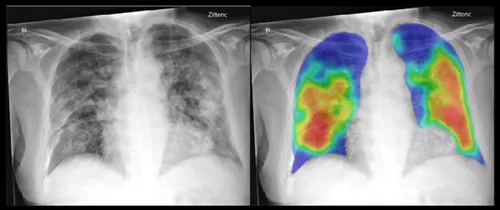

In het huidige onderzoek is gebruik gemaakt van het deep-learning* AI-systeem CAD4COVID-XRay. Er is begonnen met het systeem ‘op te leiden’met longfoto’s van andere ziekenhuizen van gezonde longen, longontstekingen, en longontstekingen veroorzaakt door COVID-19. Daarna zijn 454 röntgenbeelden van het Jeroen Bosch Ziekenhuis beoordeeld door zowel het AI-systeem als door zes radiologen. Het AI-systeem wist alle röntgenbeelden even goed te beoordelen (is op de foto een (COVID-19) longontsteking zichtbaar, of niet?) als de radiologen.

20200612 onderzoek ai covid 19